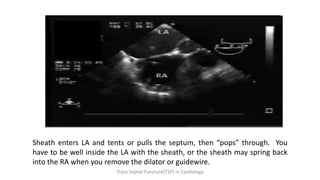

TEE Guided: Tenting Atrial Septum

Sheath enters LA and tents or pulls the septum, then “pops” through. You

have to be well inside the LA with the sheath, or the sheath may spring back

into the RA when you remove the dilator or guidewire.

TEE Guided: TentingAtrial Septum Trans Septal Puncture(TSP) in Cardiology

• 64.

Sheath enters LAand tents or pulls the septum, then “pops” through. You have to be well inside the LA with the sheath, or the sheath may spring back into the RA when you remove the dilator or guidewire. Trans Septal Puncture(TSP) in Cardiology